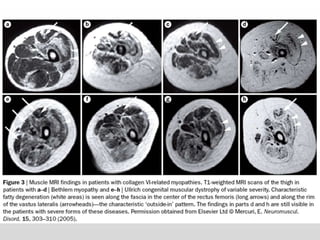

 Estudo doSono  Exame Imunoistoquímico  Cultura de Fibroblastos  Imagiologia  Diagnóstico clínico: envolvimento evidente do tecido conjuntivo Característica de um fenótipo na pele está associado com a miopatia do colágeno VI  Tendinopatia (anormalidades morfológicas nos tendões) (contribuí) Flacidez / contraturas de pequenas articulações Manifestações mais notáveis:  Queratose das superfícies (braços e pernas) – Aparência áspera  Propensão para formação de cicatriz anormal (quelóide ou atrófica)